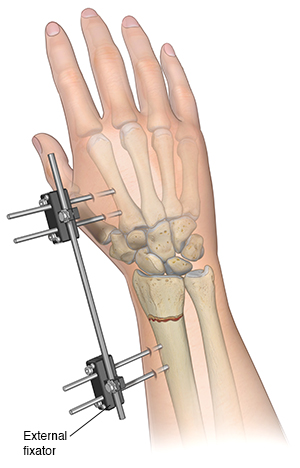

Open reduction with internal fixation is a surgical procedure that may be used in cases of badly misaligned or unstable fractures, fractures involving one of the joints in the hand, or open fractures. An open fracture is one in which the skin is disrupted over a fracture, either because the bone has poked through the skin, or there is a wound over a fracture. You may be given medicine during the procedure to let you sleep and relax your muscles. Or you may have local or regional anesthesia to numb the area involved. Your healthcare provider then makes one or more cuts (incisions) to realign the bone and fix soft tissues. Pins, screws, plates, or a combination of implants may be used under the skin to hold the bone in place during healing. Another device that may be used is an external fixator. It holds the bones in the right position. It's surgically placed on the outside of the skin. It is removed or replaced with internal fixation as the injury heals.

|

| An external fixator is a rigid bar that screws into the bone through tiny holes made in the skin. It holds the broken parts of bone in place. |

The road to healing